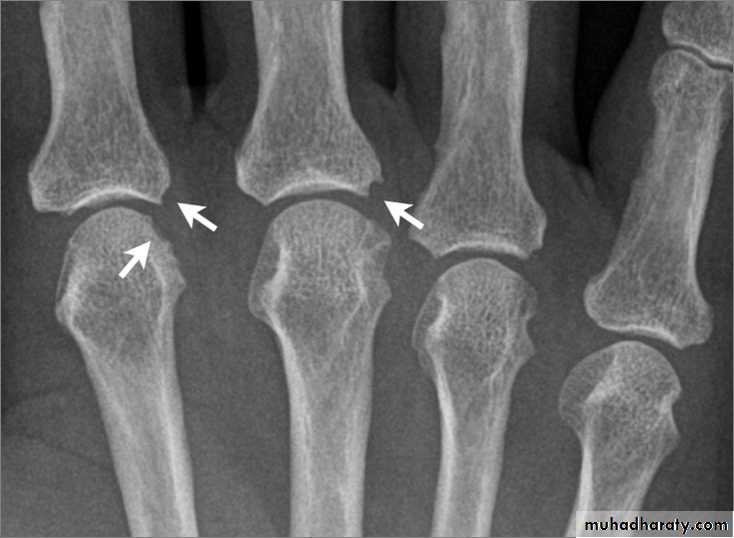

GOUT

• Heterogeneous group of entities characterized by recurrent attacks of arthritis secondary to deposition of sodium urate crystals in and around joints.• *90% of patients are male

• Radiographic features

• *Lower extremity > upper extremity; small joints > large joints

• * First MTP is most common site

• * Marginal, peri articular erosions: overhanging edge

• * Erosions may have sclerotic borders

• * Joint space is preserved

• * Soft tissue and bursa deposition

• Tophi: juxtaarticular, helix of ear

• * Erosions and tophi only seen in longstanding disease

• * Tophi calcification, 50%

• *Chondrocalcinosis